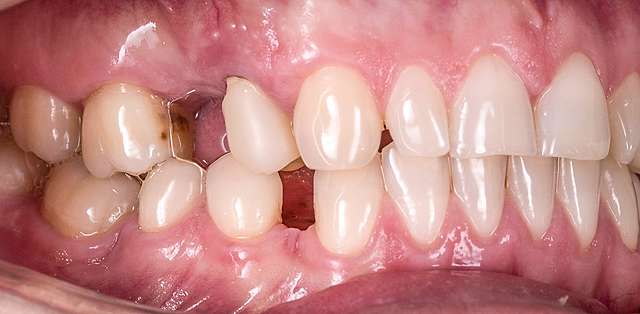

The mock-up just like a treatment plan can simulate a diverse array of procedures that vary on cases basis. In this case, we have dental implants and tissue grafts in posterior areas, on both sides, and ceramic veneers and crown lengthening in anterior side to balance the smile. As a fine detail , you can see how the dentist uses a black marker to simulate the area of the tooth which will be reduced. The mock-up, once accepted becomes a cental pillar in an interdisciplinary treatment. It will be used to determine how the gums will be remodelled , where the implants should be placed, and how the teeth need to be prepped for the future restorations.